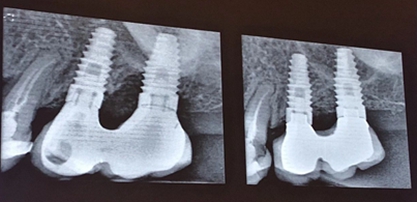

種植體周圍炎是影響牙種植遠(yuǎn)期效果導(dǎo)致種植失敗的主要原因之一。和天然牙一樣,如果口腔衛(wèi)生不良,菌斑滯留,那么細(xì)菌微生物就會對種植體周圍的軟組織不斷刺激,使機(jī)體產(chǎn)生炎癥反應(yīng),表現(xiàn)為黏膜的紅腫、探診出血甚至溢膿。也可通過X片來評估種植體周圍的骨量情況。

手術(shù)方式治療則需通過翻瓣清潔種植體及修復(fù)體上菌斑牙石,推薦在此過程中使用士卓曼鈦刷,因?yàn)樵撯佀⒉粫p傷種植體表面細(xì)微結(jié)構(gòu)。之后進(jìn)行植骨蓋膜來促進(jìn)種植體周圍吸收部分的骨的重建。